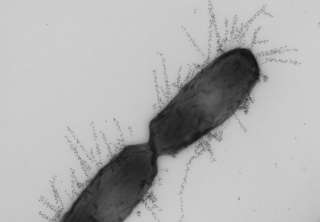

ヒトは腸内細菌と共生し、多大な恩恵を受けている(写真はイメージ)

ヒトは腸内細菌と共生している

ところで、わたしたち各人の腸にはなんと100兆もの微生物がいる。そして、彼らはわたしたちにただ便乗しているのではなく、わたしたちに多大な利益をもたらしてもいる。